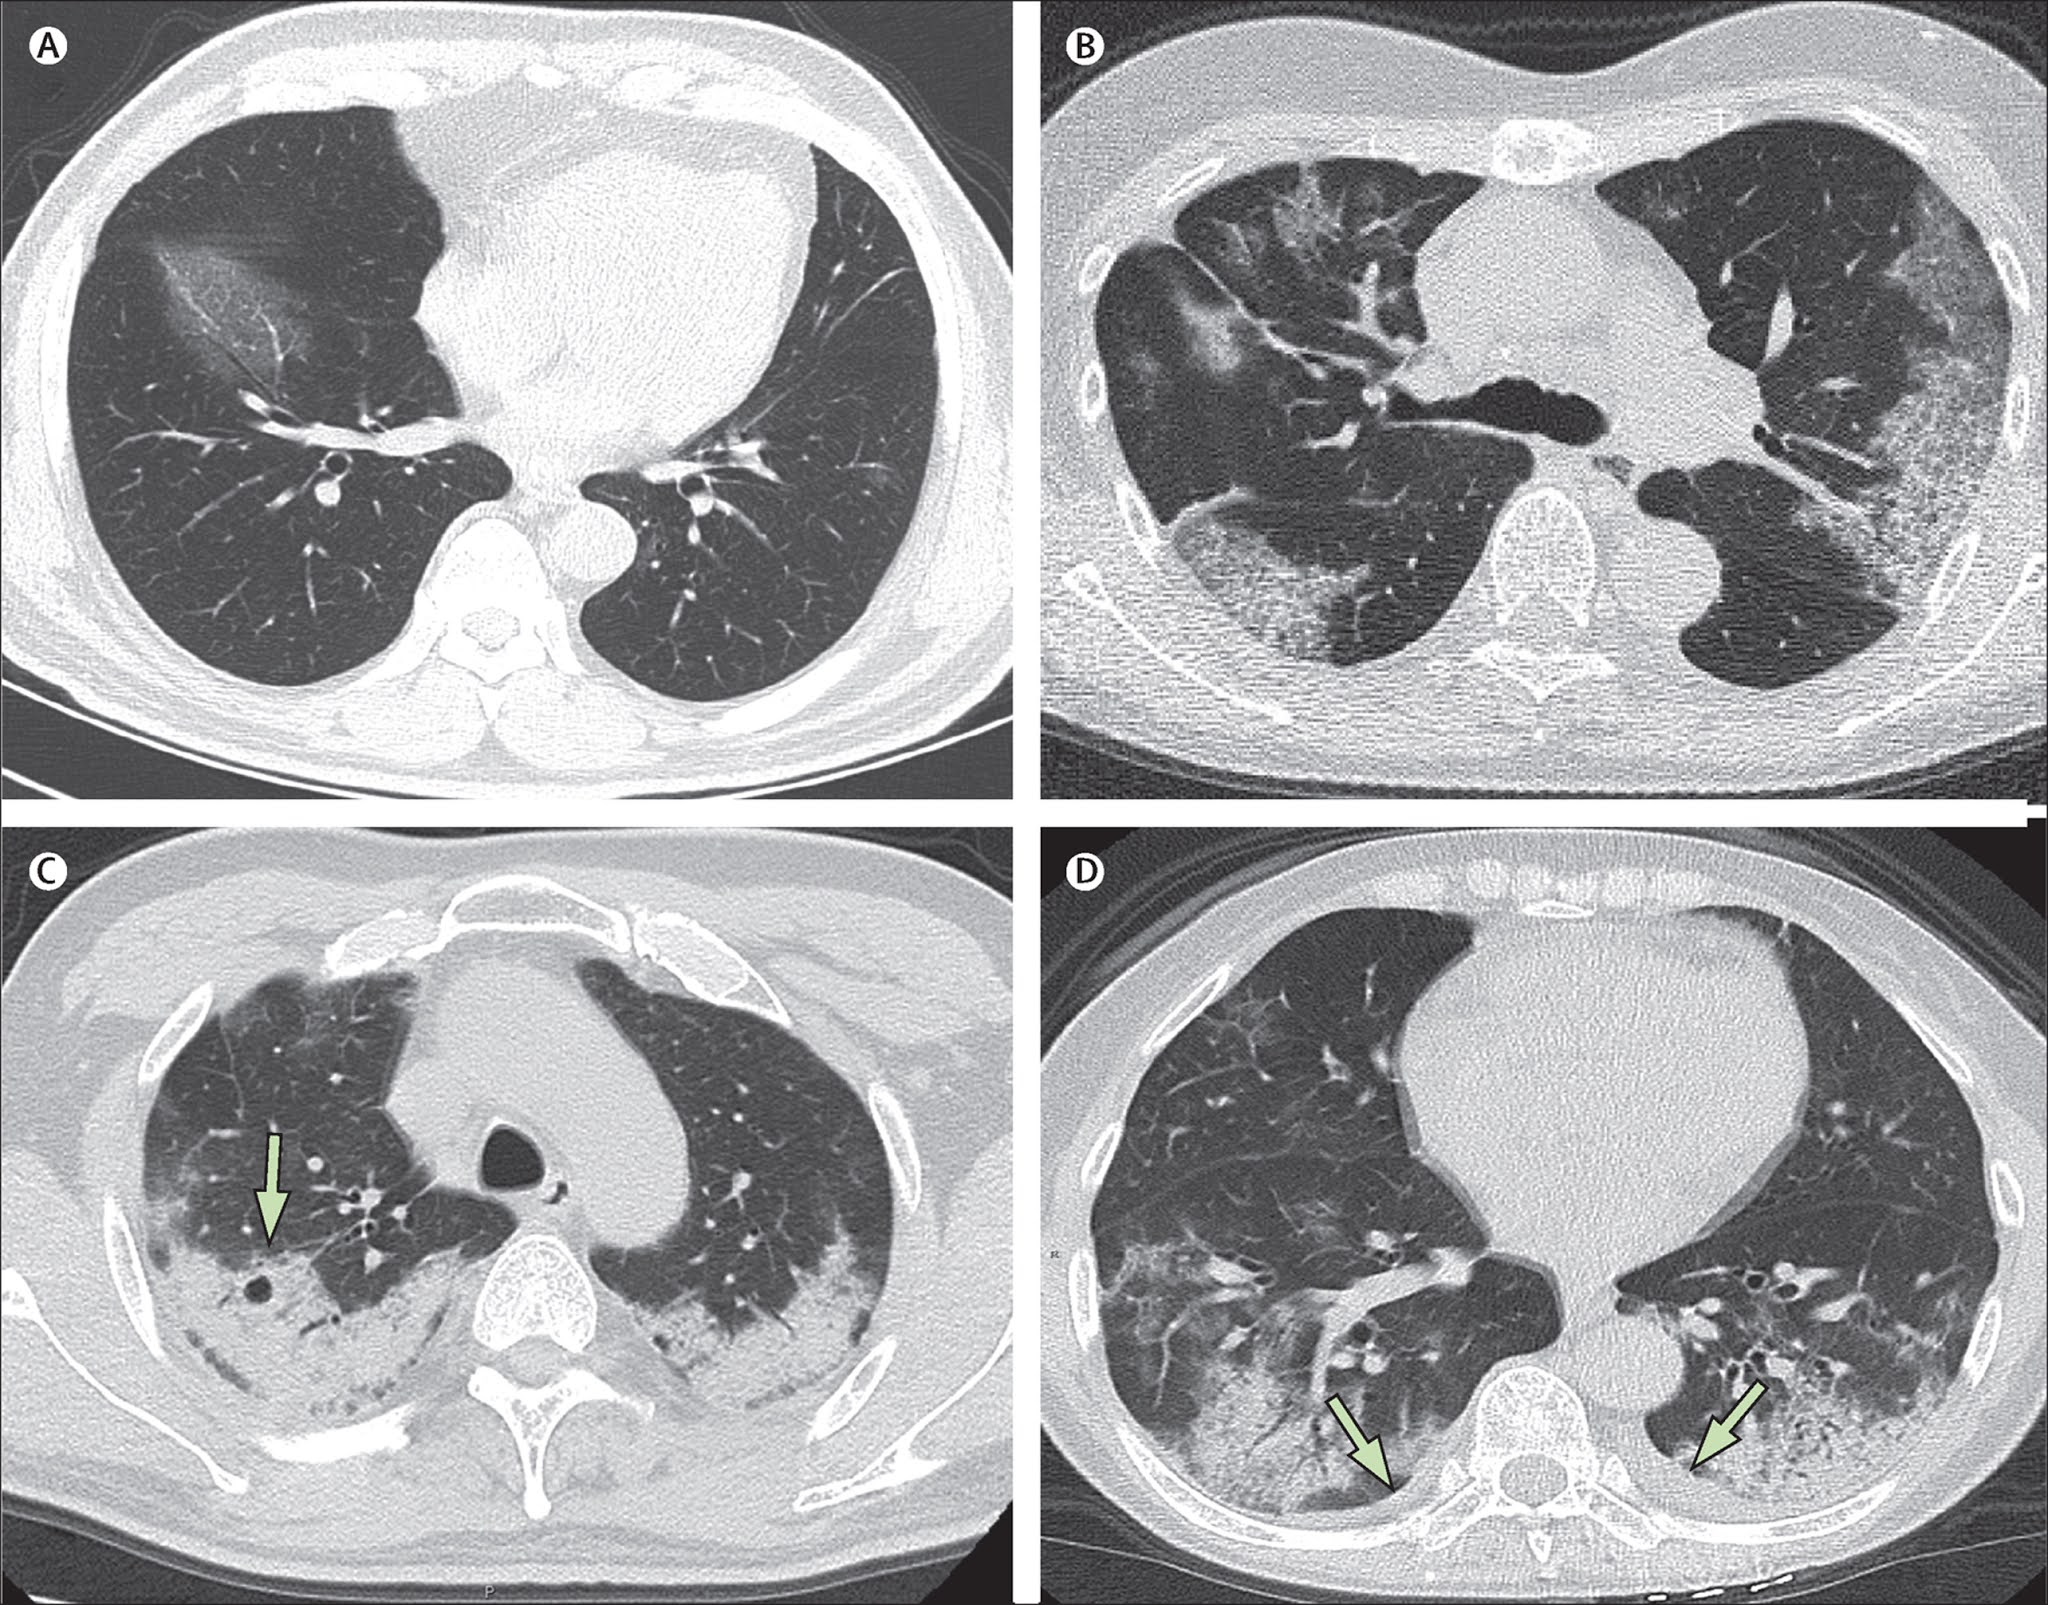

The patient’s history and physical examination are important components of the diagnosis and may indicate symptoms that are consistent with CAP, immune dysfunction, and/or potential exposure to specific pathogens. However, a definitive diagnosis of pneumonia requires confirmation of the presence of a new infiltrate on a chest x-ray.

Imaging methods

Chest x-rays should be ordered as soon as possible in all patients hospitalized with suspected NGP to confirm or rule out the diagnosis.

In general, a chest x-ray is not mandatory for outpatients with suspected NGP. Direct and oblique lateral projections increase the likelihood of diagnosing pneumonia and are useful in establishing the severity of the disease.

The benefit of chest x-ray in the diagnosis of CAP has been questioned by studies using lung ultrasound and computed tomography (CT) of the chest. Lung ultrasonography should be considered if the chest x-ray is negative and the patient is elderly and frail, or clinical suspicion is uncertain.[72] Niederman MS. Imaging for the management of community-acquired pneumonia: what to do if the chest radiograph is clear. Chest. 2018 Mar;153(3):583-5.

Chest CT scan should be considered in patients with an indeterminate diagnosis after chest x-ray and ultrasonography.[72]Niederman MS. Imaging for the management of community-acquired pneumonia: what to do if the chest radiograph is clear. Chest. 2018 Mar;153(3):583-5.

Chest CT may improve the diagnosis of NGP because chest x-ray can lead to a misdiagnosis.

Chest CT provides detailed information about the condition of the parenchyma and lungs, as well as the mediastinum. However, major limitations include exposure to radiation, high cost, and the inability to perform bedside examinations. One study showed that in patients presenting to emergency departments with suspected NGP, early CT scan results, if CT is used as an adjunct to chest x-ray, significantly affect both diagnosis and clinical management.[ 78] Claessens YE, Debray MP, Tubach F, et al. Early chest computed tomography scan to assist diagnosis and guide treatment decision for suspected community-acquired pneumonia. Am J Respir Crit Care Med. 2015 Oct 15;192(8):974-82.